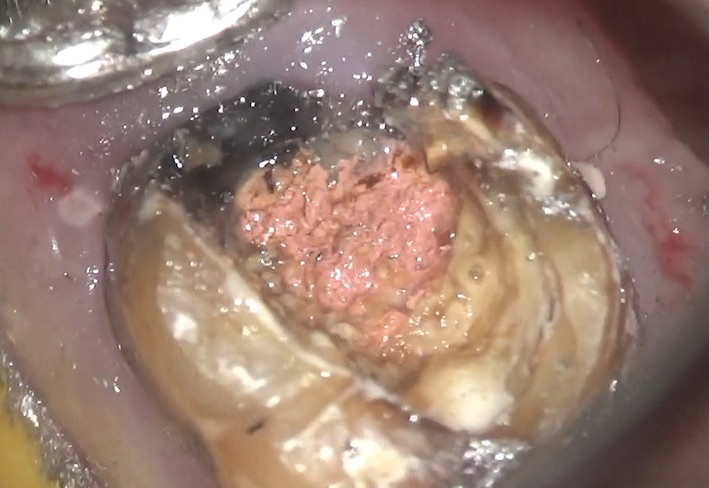

この金属を、マイクロスコープを用いて外していくと・・・

なにやら、すぐに土台が動いた感覚がありました。専用の道具で外れるような力をかけると、

すぐ、ポンと外れてしまいました。内部では虫歯がかなり奥まで進行していました。

この患者さんの歯、虫歯が進行しすぎて、通常では残せないので、歯茎の部分を修正する手術をしました。それほど症状が進行していたのです。